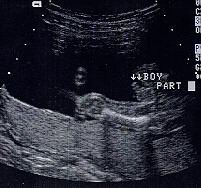

IT'S A BOY !!